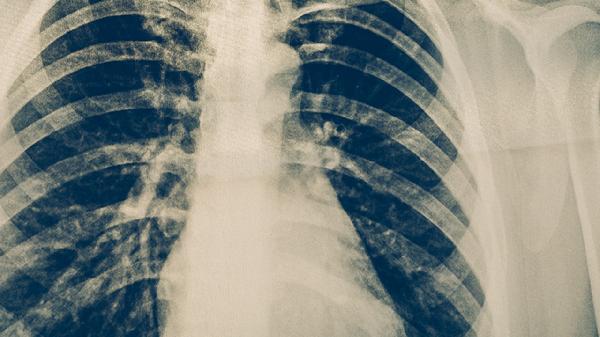

4、定期复查

治疗期间每月需进行痰涂片检查和胸部X线评估,治愈后仍需每年随访2年。复查可及时发现复发征兆,耐药患者需根据药敏试验调整方案。合并糖尿病等基础疾病者需加强血糖监测。